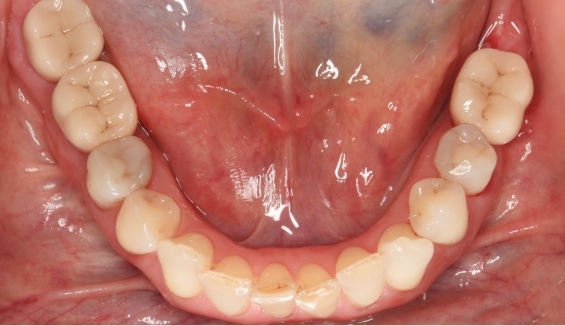

Versatile in their applications, ceramic implants can be used for single-tooth replacement, multiple teeth, or full arch restorations, catering to various dental needs. Beyond aesthetics, they provide stable support for dental restorations, allowing patients to eat, speak, and smile with confidence and comfort.